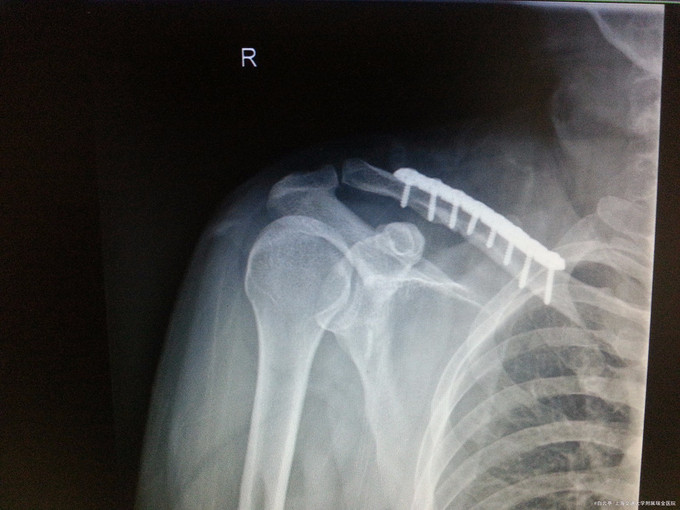

诊断:右侧锁骨骨折 处理:右锁骨骨折切开复位钢板螺丝钉内固定术

随访:术后2周患者手术切口愈合好,肩关节活动及功能良好。 讨论:锁骨中段骨折的治疗是否手术常有争议,请各位讨论自己的观点。